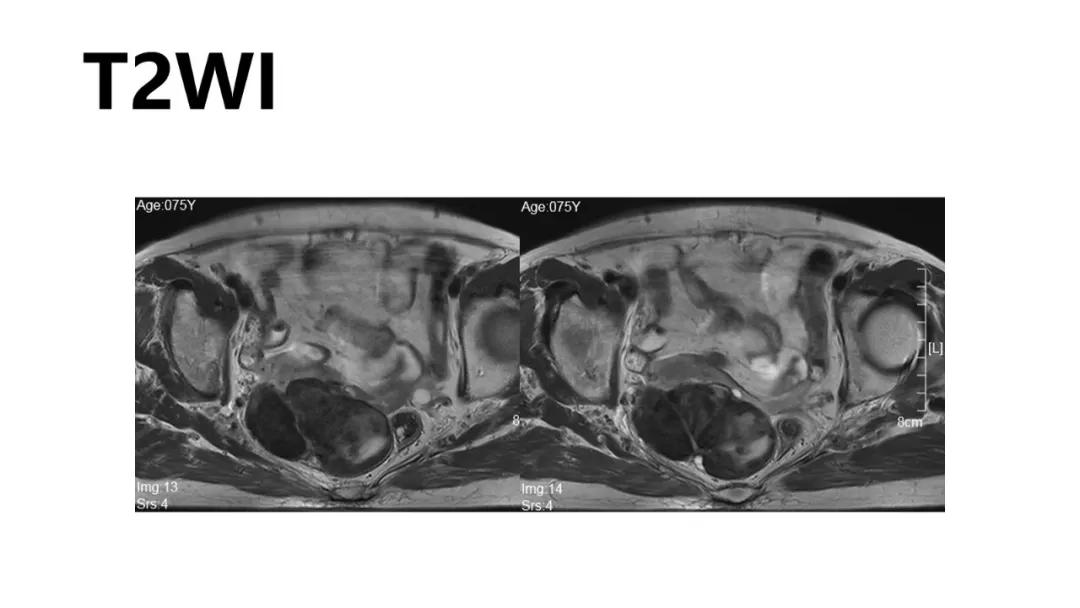

病理:左侧卵巢卵泡膜-纤维瘤